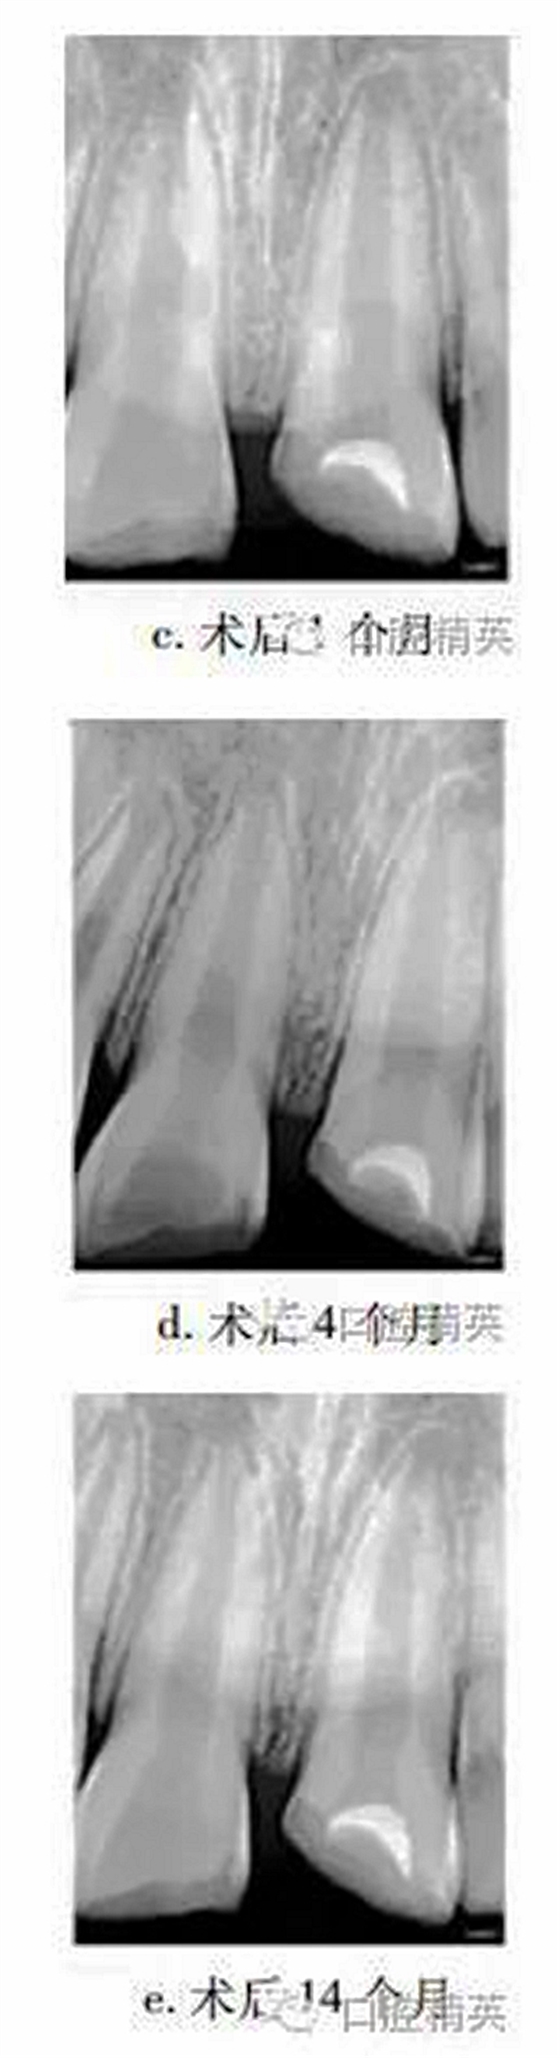

1個月后復查,21無明顯不適,上唇腫脹減輕,患牙冷熱診(-),牙髓電活力測試(-),X線片示根尖無明顯變化(圖c)。4個月后復查,患牙無明顯不適,冷熱診(±),牙髓活力測試(-),X線片示患牙根管腔略見縮窄(圖d)。14個月后復查,患牙無明顯不適,牙髓活力測試(+),但較正常對照牙低;X線片示:蓋髓劑下方可見斷斷續(xù)續(xù)的高密度影像,根管壁增厚,管腔明顯縮窄,根尖孔聚攏傾向,牙根長度較初診時增加(圖e)?;佳涝涮钗锫杂腥睋p,稍加預(yù)備后玻璃離子暫時恢復牙冠形態(tài)。